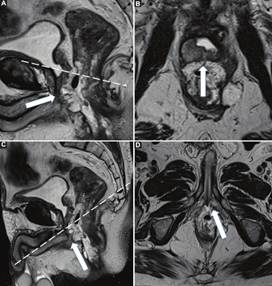

Primero, se realizó el plano sagital estricto para poder identificar la lesión; una vez visualizada esta, se planificó el plano axial oblicuo, perpendicular al eje tumoral, permitiéndonos visualizar su correcta relación con las estructuras anatómicas vecinas.

Con respecto al plano coronal oblicuo, en los casos en donde hubo compromiso únicamente del recto medio y/o superior se realizó siguiendo el eje longitudinal tumoral, mientras que cuando existía compromiso del recto inferior se planificó siguiendo el eje longitudinal del canal anal, permitiéndonos definir en forma adecuada el compromiso del complejo esfinteriano. En aquellos casos en que el tumor comprometía al recto inferior y medio, optamos por adquirir dos planos coronales, uno siguiendo al canal anal y otro al eje longitudinal tumoral en recto medio.